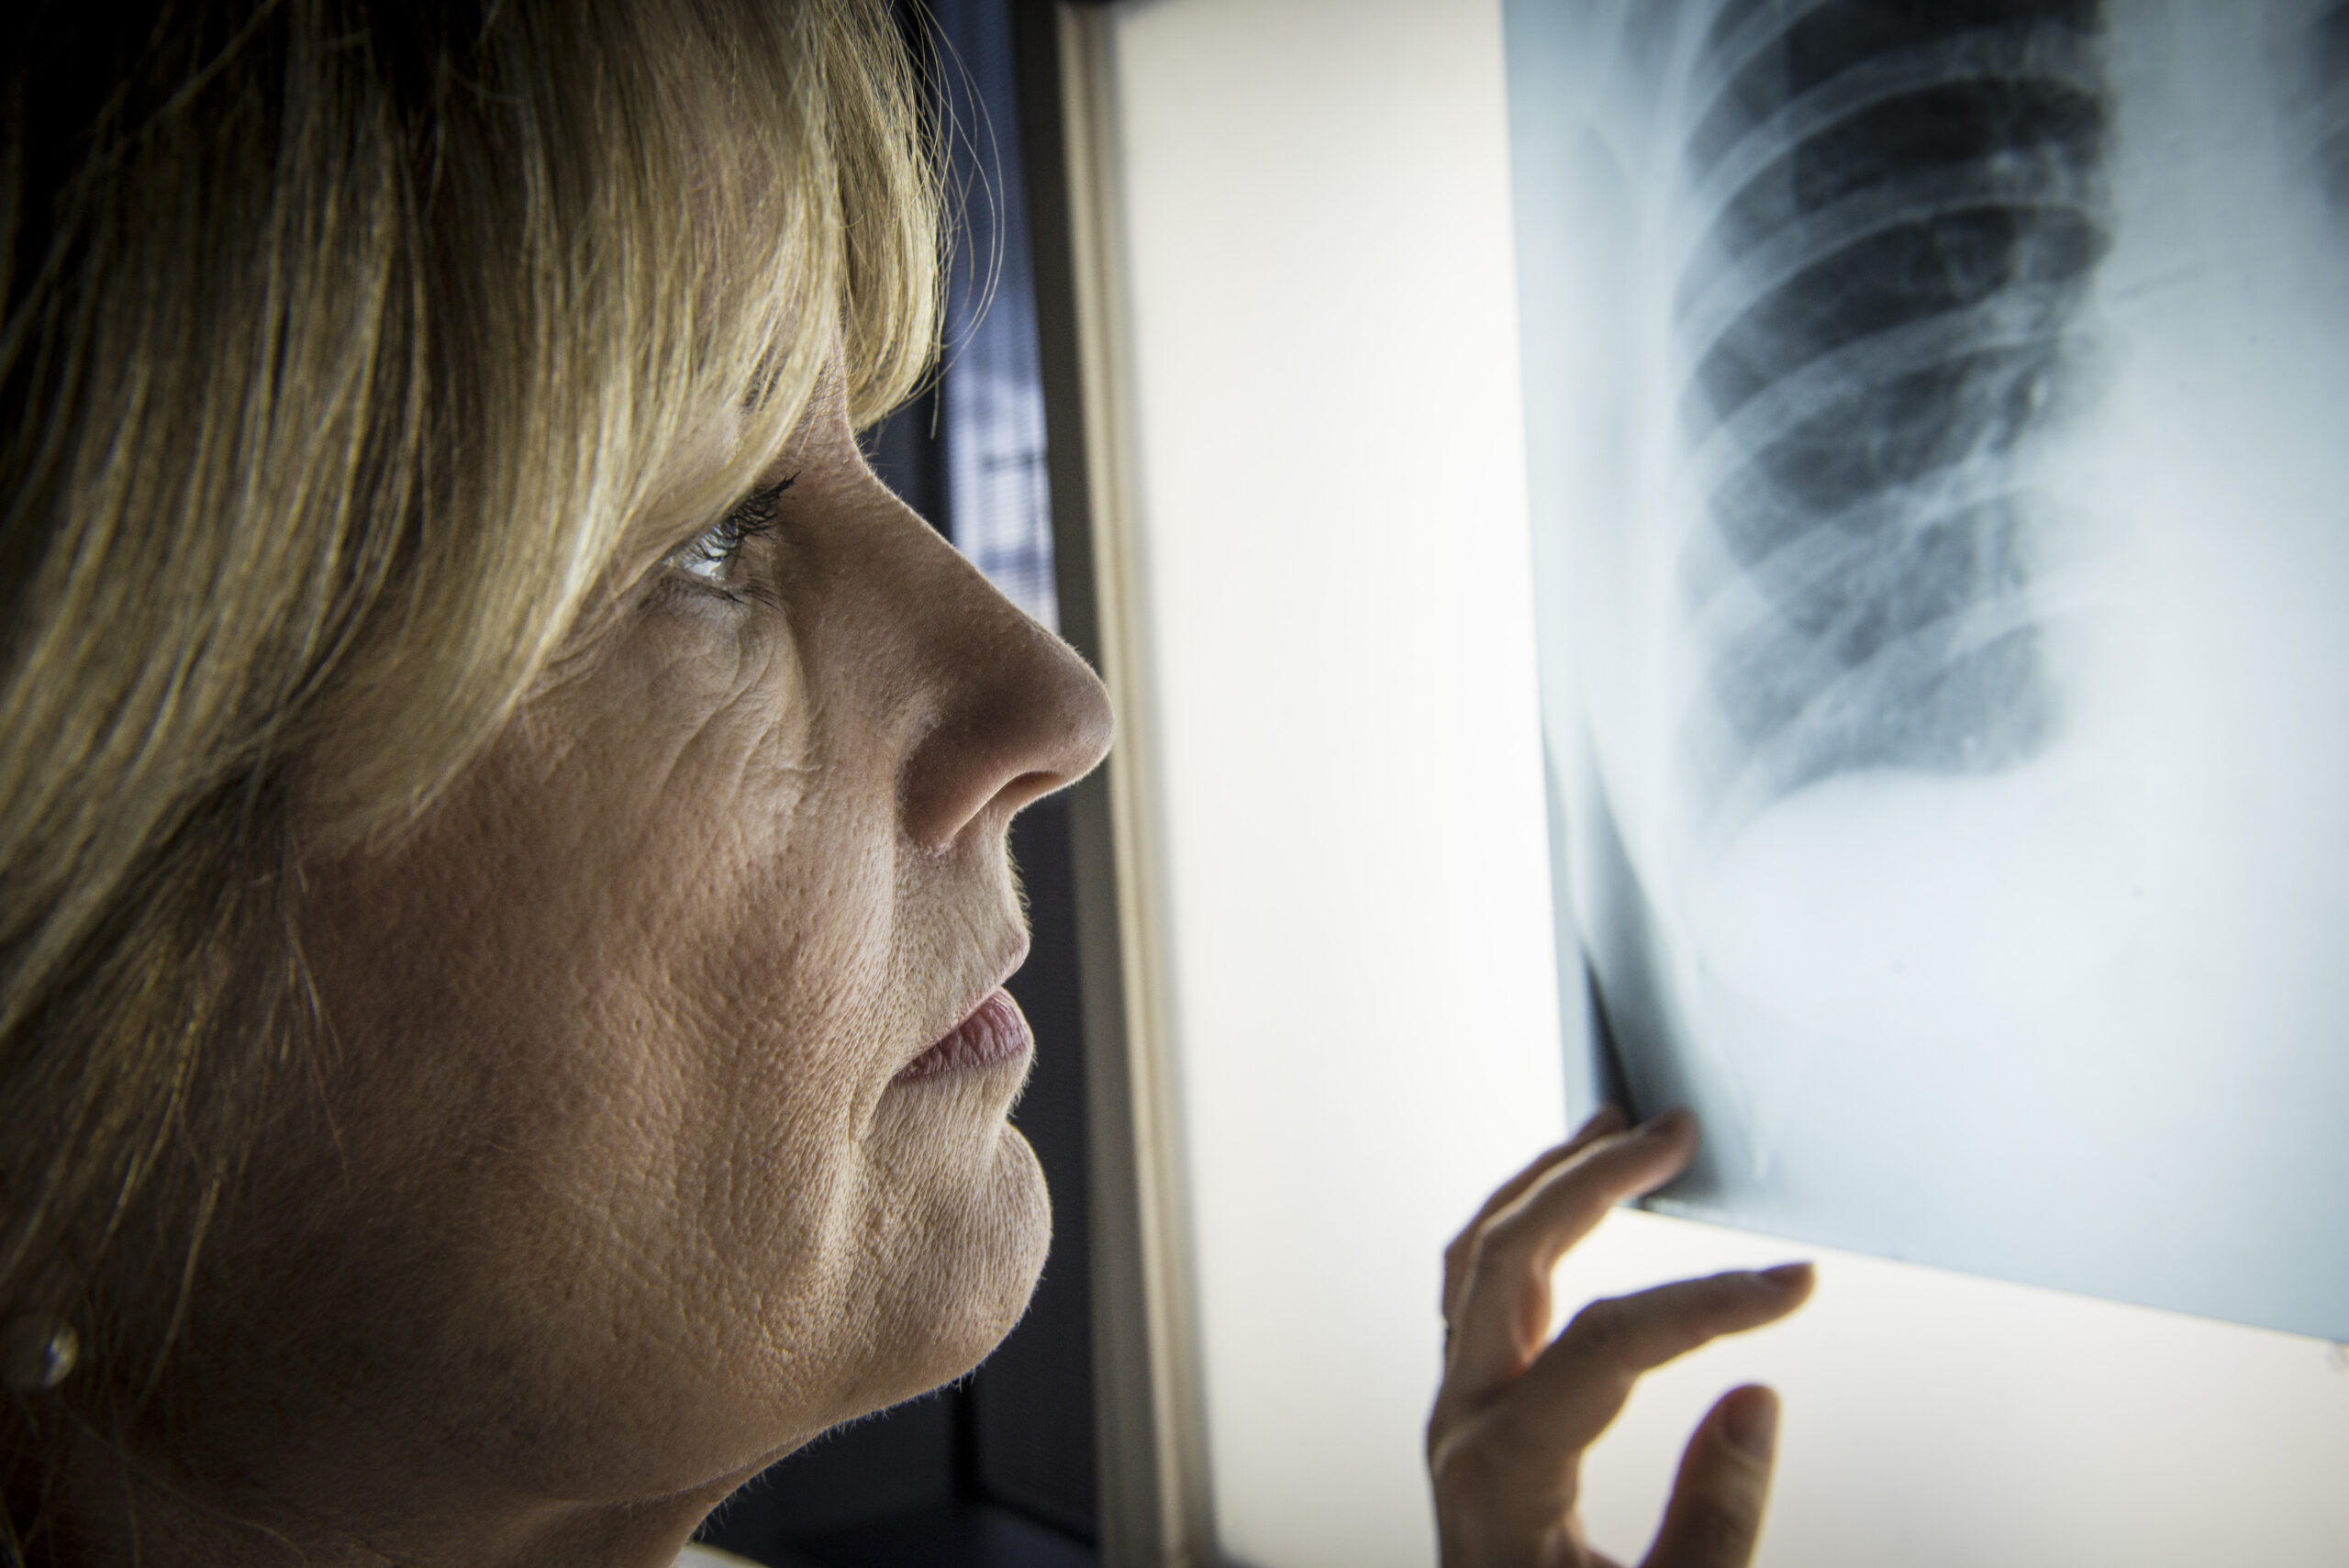

“Es importante reconocer los signos y síntomas que podrían sugerir la presencia de la enfermedad. Su diagnóstico debe ser estudiado y confirmado por exámenes médicos como la espirometría que es una prueba de función pulmonar, rayos X en el tórax, tomografía, análisis de los gases de la sangre arterial y otras pruebas de laboratorio”, concluyó Ramírez.